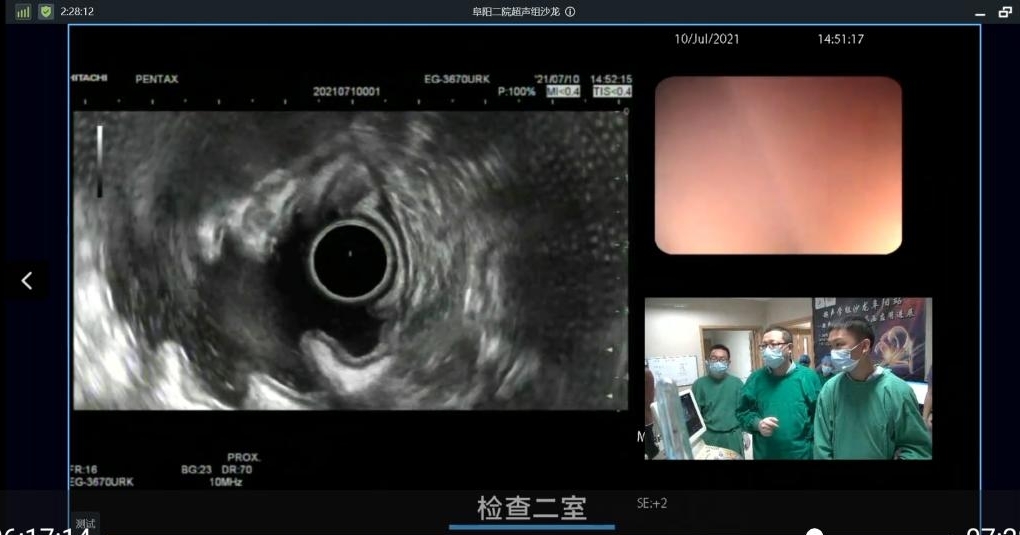

随后,在阜阳市第二人民医院消化内镜中心现场开展了共20例内镜下治疗,并通过网络直播在小鱼易连以及消化新境界公众号推送,全国热心于该项技术的5000余人观看了直播。

陈洪潭教授就胃底静脉曲张及食管静脉曲张超声内镜下诊疗进行操作,并通过网络向全国的同道们分享了自己的心得,以及在处理静脉曲张时的注意事项和技巧。

吕瑛教授通过现场操作,和同道们分享了超声内镜在静脉曲张中的规范应用及注意事项,提出了个人多年的工作经验,并就粘膜下肿瘤超声下诊断治疗做了分享。

宋继中教授演示并指出超声内镜的精准优势,进行手把手带教